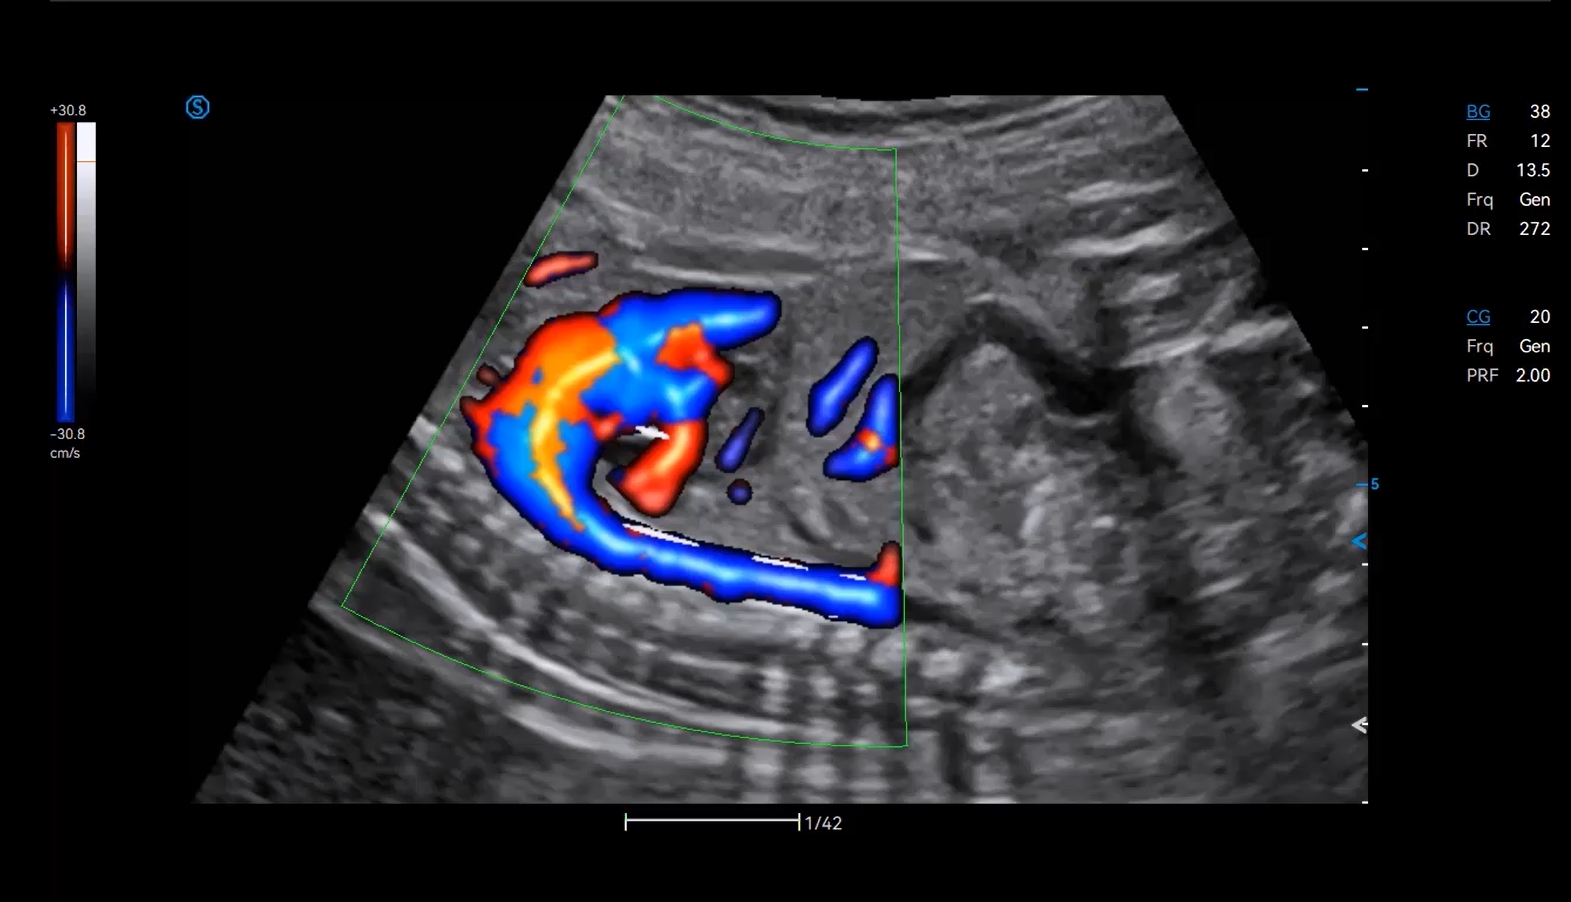

- Category: Color Doppler

- More accurate and convenient for diagnosing solid-cystic tumors